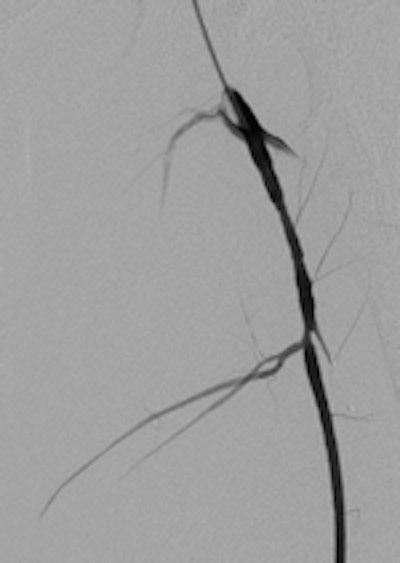

A 19-year-old male with delayed presentation following gunshot injury in the thigh. Left: T1 coronal MRI shows a large pseudoaneurysm in the upper thigh. Pre- (middle) and postembolization (right) angiographic images demonstrate successful treatment of the pseudoaneurysm.The two mechanisms of tissue injury that account for the majority of damage caused by a bullet are direct crushing of tissue by the projectile (causing a permanent cavity) and temporary cavitation, which stretches and tears surrounding tissues. Increased velocity, fragmentation, deformation, and rolling/spinning of the bullet will cause more damage by both these mechanisms, he pointed out.